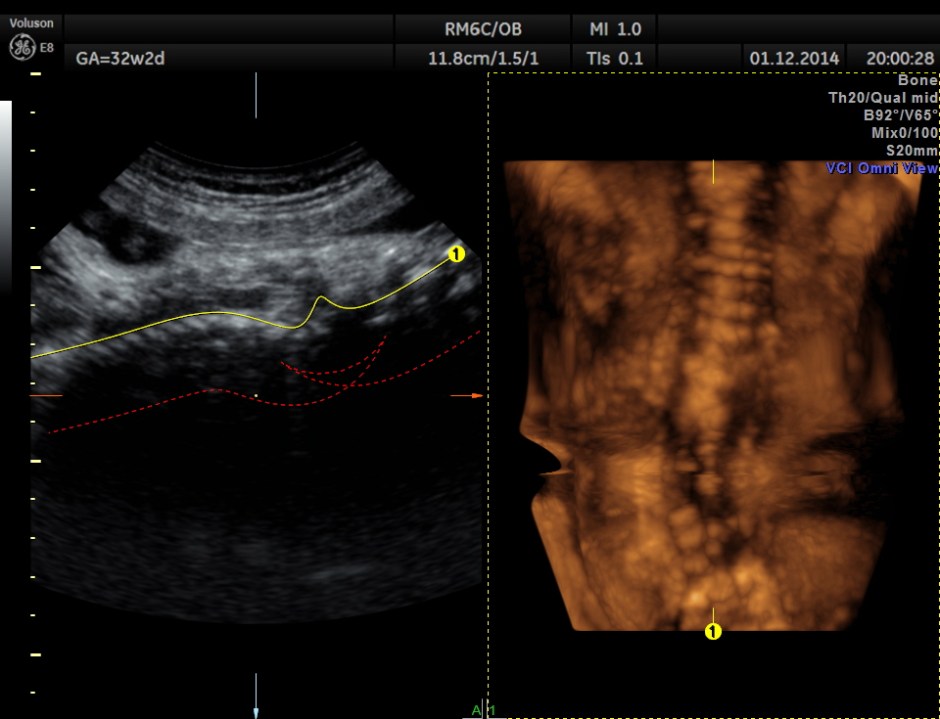

This was a 30 year old lady , with history of consanguinity ; 2nd gravida , 1st child normal ; she has never gone for an ultrasound examination in this pregnancy and was sent by her consultant to a different centre for evaluation . She was found to have hydrocephalus and was referred to our clinic for 2nd opinion.

The following images were obtained.

Hydrocephalus is seen ; Cisterna magna appeared somewhat compressed.

3D view of the same.

Careful examination revealed a neural tube defect with meningo myelocele at the lumbo sacral level.

Spinal deformity was also noted.